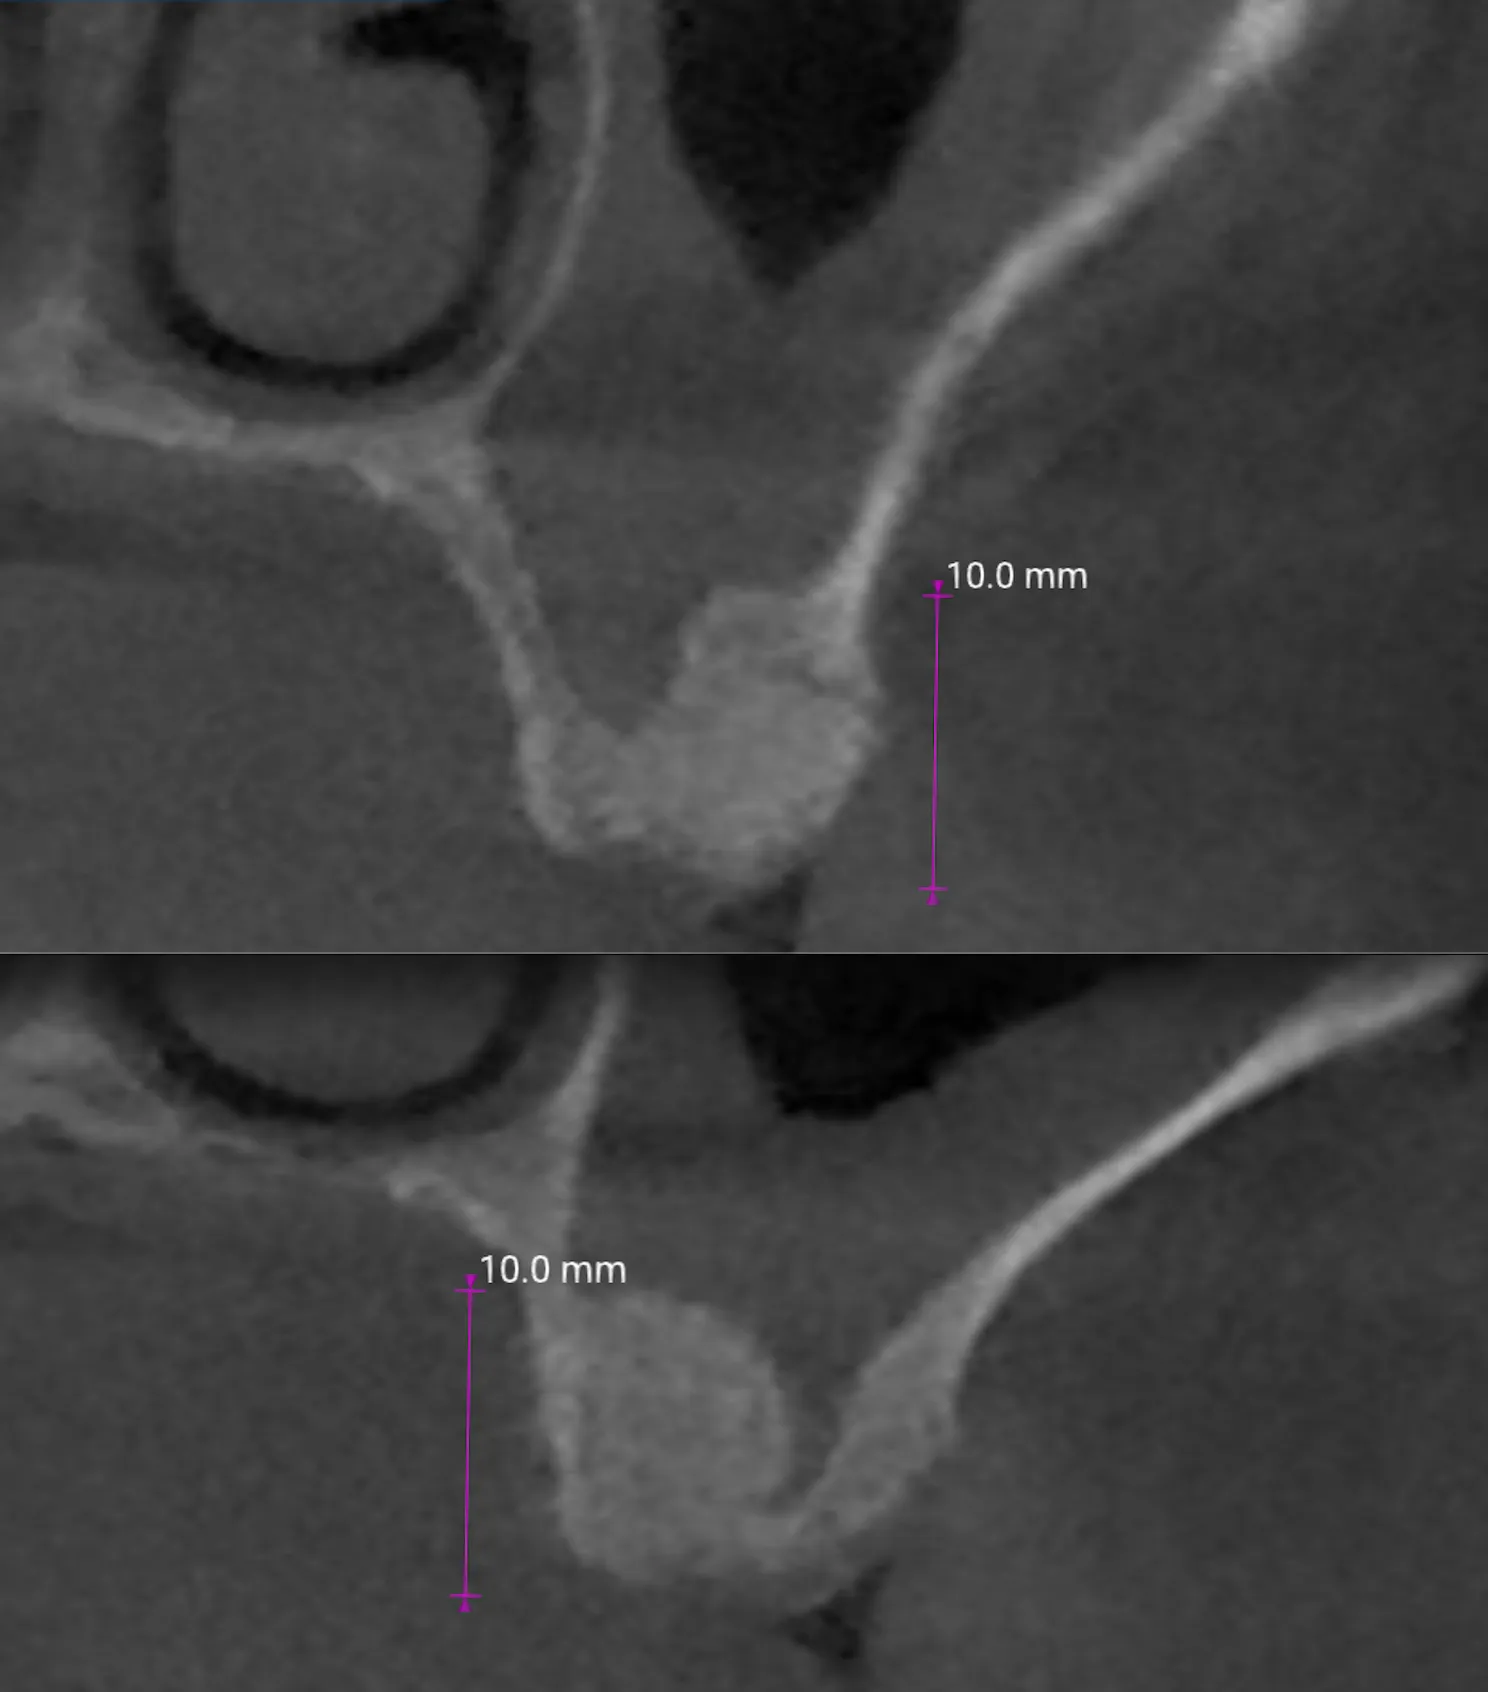

Quanto osso si guadagna con questa tecnica?

Dipende dalla conformazione anatomica e dall’altezza residua di partenza. Nel caso presentato, il follow-up CBCT a 2 mesi mostra un rialzo di circa 10 mm. La letteratura riporta risultati predicibili anche in creste con altezza residua inferiore a 5 mm, con tassi di sopravvivenza implantare del 95,81% a 5 anni (Del Fabbro et al., 2012).